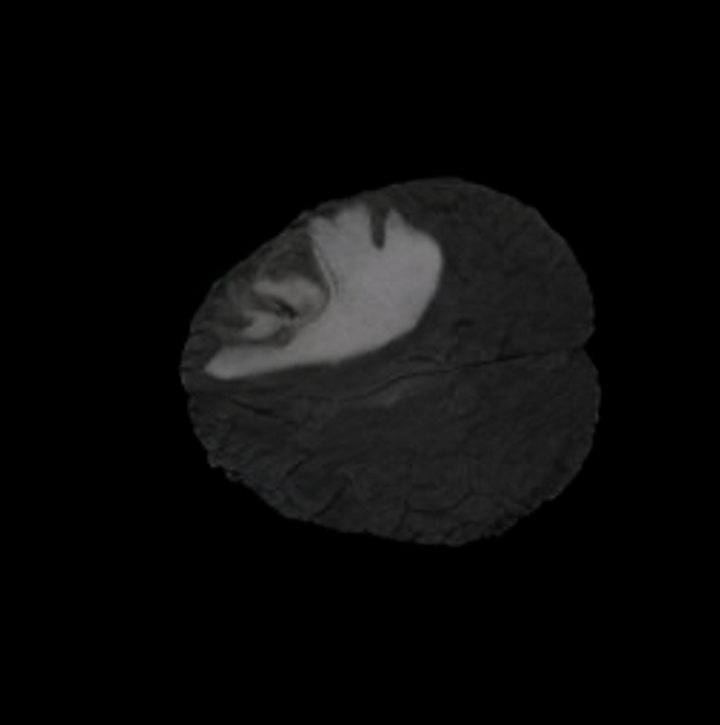

To see when and how X-Diffusion fails, we conducted an experiment on healthy brains (no tumour) using IXI dataset, by running an X-diffusion trained on BRATS brain tumor dataset. Our X-Diffusion achieved a PSNR of 35.86 dB on the IXI dataset despite being trained on the BRATS dataset. We then ran the tumour segmenter on the set of 582 healthy scans and corresponding generated MRIs. The segmenter predicted tumours in 9.9% of the real healthy brains and in 11.3% of the generated brain MRIs. Some of these tumor hallucination examples fron X-Diffusion generation are shown in Figure 10.

| Hallucination | Reference | Hallucination | Reference | Failure | Reference |